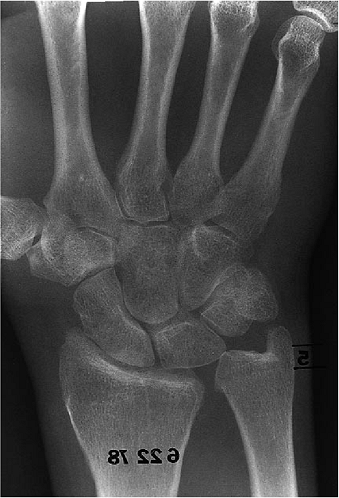

A 33-year-old man had persistent radiocapitellar pain with an associated radioulnar impingement (Fig. 23-23)

after radial head excision and distal radioulnar symptoms from an ulna

plus deformity from the Essex-Lopresti lesion. From radial shortening (Fig. 23-24) the anconeus is brought under the collateral ligament (Fig. 23-25),

which, because it was insufficient, required further stabilization by

reinforcement with a Krachow stitch; an ulnar-shortening procedure was

also completed (Fig. 23-26). The patient had minimal pain at the wrist and elbow, and no symptoms of impingement at the elbow at 1 year (Fig. 23-27).

Figure 23-23. A 33-year-old male had painful radiohumeral symptoms after fracture dislocation with radial head excision.

|